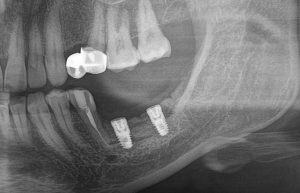

Результат остеопластики методом остетотомии мы можем оценить уже через 4 месяца. Перед этим сделаем контрольные снимки (слева «до», справа «через 4 мес»):

Вроде как, всё неплохо. Наверное, можно поставить имплантаты?

ну, или как-то так:

При этом, я хотел бы обратить ваше внимание на один важный момент. То, с чем вы сейчас работаете — не кость, в привычном нам гистолого-физиологическом понимании. Это костная мозоль вперемежку с графтом. Её свойства довольно сильно отличаются от того, что мы привыкли называть костной тканью. Поэтому при установке имплантатов соблюдайте максимальную осторожность и щадящий режим. Никаких диких торков, усилий, больших переходов между размерами фрез допускать нельзя. Будьте аккуратны.